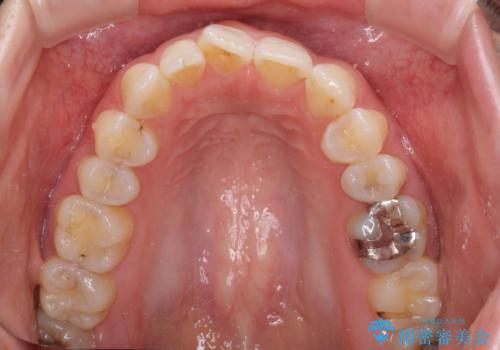

- 矯正治療の後戻りが気になるとのことで来院された患者様です。

上顎の後戻りをインビザライン・ライトで治療することとしました。

上顎のみの治療を希望されたため、咬み合わせをしっかりと改善することはできませんでしたが、審美面が大きく改善され、日常生活の機能面でも不具合を感じることはなく、大変満足していただきました。